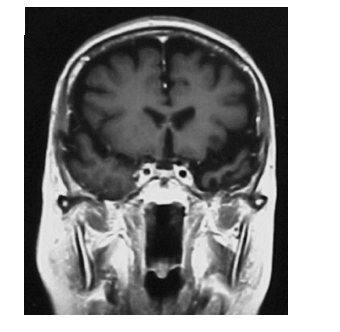

A imagem de um corte frontal mostra um paciente com demência semântica, em que se observa